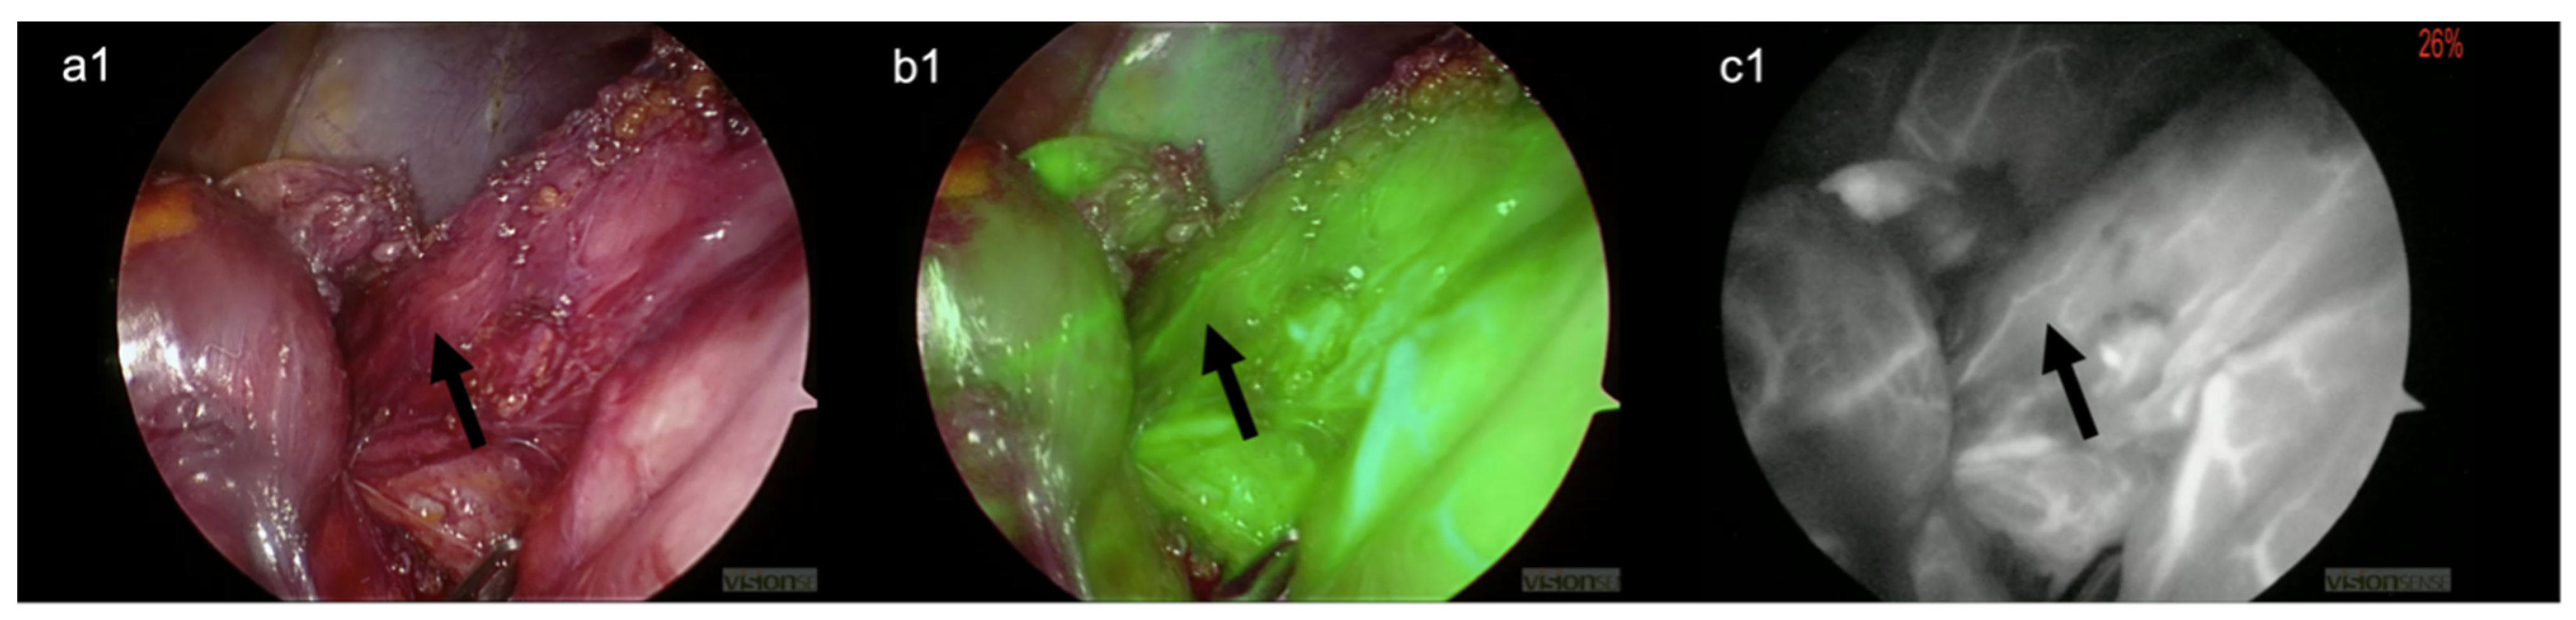

2. Surgical Technique